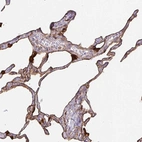

Immunohistochemistry analysis in human lung and cerebral cortex tissues using Anti-ANXA2 antibody. Corresponding ANXA2 RNA-seq data are presented for the same tissues.